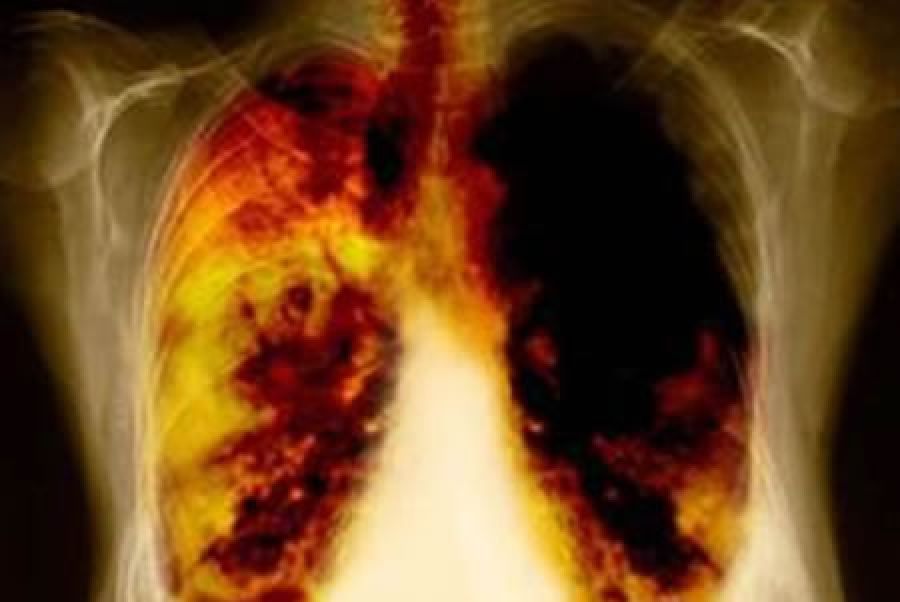

De acuerdo con Respirando con Valor A.C., organización que forma parte del movimiento nacional “Juntos Contra el Cáncer” el 95% de los casos de cáncer de pulmón se detectan en etapas avanzadas (III y IV) y entre el 80-97% de los mexicanos con esta enfermedad mueren en el mismo año en que fueron diagnosticados.1

Además, el cáncer de pulmón es el más letal de todos los tipos de cáncer. En México, la incidencia y mortalidad, calculadas en el año 2012, fueron 7.5 y 6.7 casos por cada 100,000 habitantes, respectivamente. Cada año, a nivel mundial, más gente muere por cáncer de pulmón, que por cánceres de colon, mama y próstata combinados.2

De acuerdo con datos de Globocan, el cáncer de pulmón ha sido el cáncer más común durante varias décadas y se estima que es responsable de casi una de cada cinco muertes en el mundo (1.59 millones, el 19.4% del total por esta enfermedad).